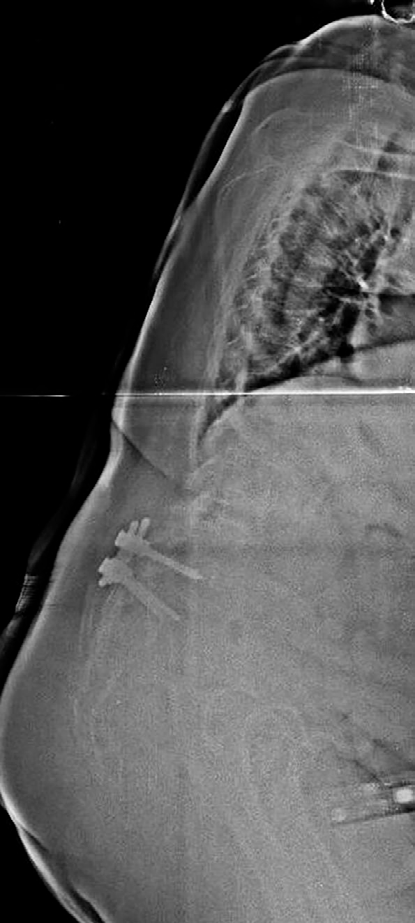

Paciente intervenida de fusión espinal desde T4 hasta hueso ilíaco, además de laminectomía y artrodesis circunferencial TLIF en L3-L4 y L4-L5, por desequilibrio sagital que condicionaba incapacidad a la bipedestación, pérdida de fuerza y disestesias en miembro inferior izquierdo (MII). En el postoperatorio inmediato presenta incapacidad para extender la rodilla izquierda. La neuromonitorización intraquirúrgica (IOM) con potenciales evocados somatosensoriales (SSEP) y potenciales evocados motores (MEP) solo mostraron ligera latencia alargada en SSEPs de lado derecho.

- TC: estenosis foraminal bilateral de T8, ligera medialización de tornillo L3 sin invadir canal medular.

- RMN: no estenosis crítica de canal raquídeo ni signos de lesión medular.

Se realizó cirugía de revisión con foraminotomía y laminectomía L2-L3, laminectomía completa L3-L5 confirmando liberación completa de raíces izquierdas L2 a L5, además de laminectomía T8-T9.